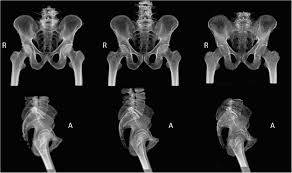

Thirty nine patients with abnormal pelvis were compared with ct and ultrasounds. This provides an excellent look at the large and small bowel. Über 7 millionen englischsprachige bücher. The musculoskeletal system is responsible for form, support, stability and movement. This is a higher quality study than a standard ct. Tanksi and jordan ruby the rich vascular supply of the pelvis not only supports the structures contained within it, including the bladder, rectum, and reproductive organs, but also extends to the lower extremities. Mri of the female pelvis: Ascending colon superior mesenteric vein superior mesenteric artery gonadal vessels linea semilunaris abdominal aorta linea alba inferior vena cava inferior mesenteric artery infe. Anatomy ct axial abdomen and pelvis male male abdomen and pelvis ct scan form no 1. Two radiographic views of the cat's pelvis are used to confirm the diagnosis of pelvic fractures and may also show sacroiliac luxation (dislocation), coxofemoral luxation, or femoral fracture if they are present. 6.1a, b) is a bony ring consisting of paired innominate bones, the sacrum and coccyx. These radiographs of animal anatomy are under the copyright of imaios and can not be freely used. Page 1 of 15 (wow) bony pelvis anatomy skeletally radiographs ct protocols pelvic ring fx sacrum